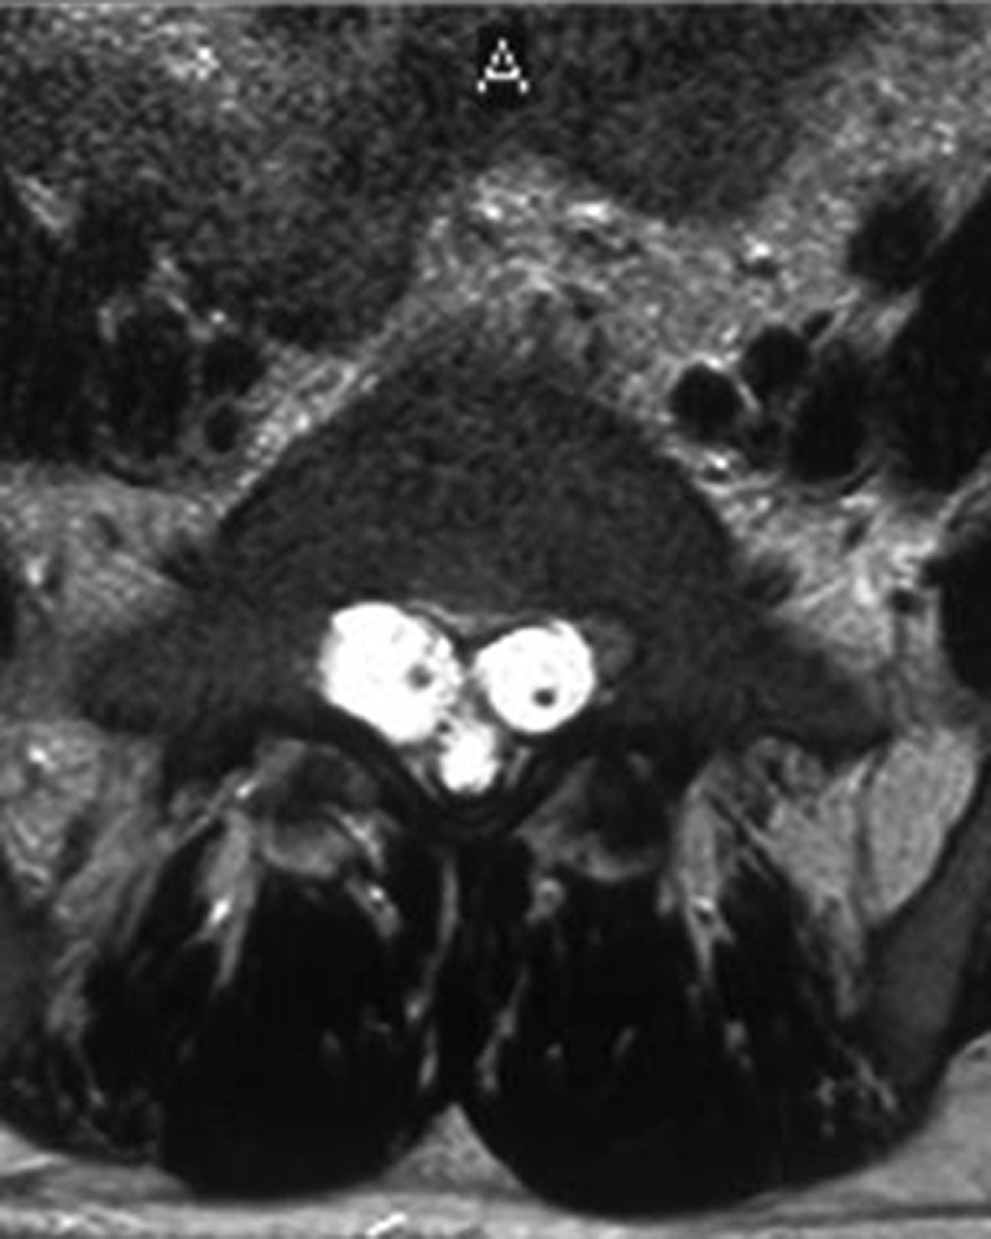

Results: All cystic lesions showed hypointense signal intensity on T1WI and hyperintense signal intensity on T2WI, but the nerve root showed iso-intensity on T1WI and low signal intensity on T2WI. They were linear in shape on sagittal view, and hypo intense dotted spots within the cysts on traverse view. Surrounding structures of the larger cysts were compressed and had bone erosions in some cases; the spinal canal and the intervertebral foramen on the affected side were enlarged. The lesions/cyst wall showed no enhancement after gadolinium administration.